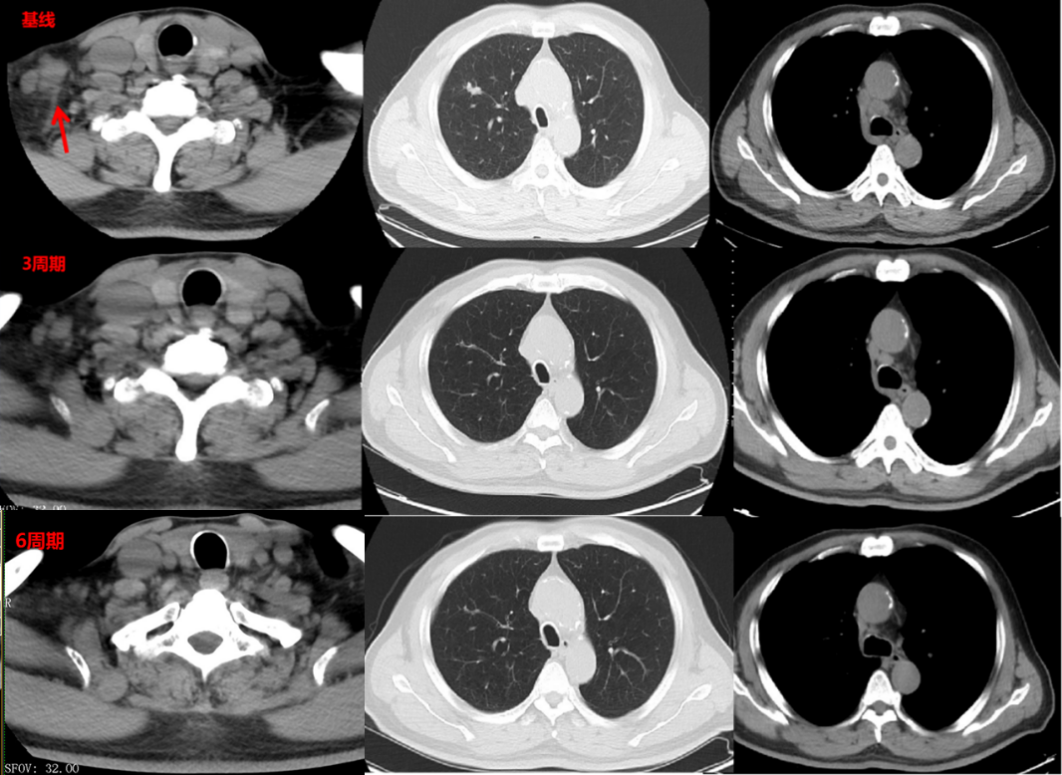

疗效评估:3周期后、6周期后分别行颈胸部CT,病灶较前明显缩小,肿瘤标志物显著降低,疗效评价:PR。

图片21.png

影像学检查图像(基线、3周期后、6周期后)

在一线免疫联合化疗的过程中,患者在3周期后即达到PR的疗效,肿瘤标志物显著下降,体现了斯鲁利单抗联合化疗一线治疗方案具有强效的抗肿瘤治疗效果,6周期后疗效评价维持PR,后续予单药免疫维持治疗至今已达3年,展现出斯鲁利单抗持久且稳健的肿瘤控制潜力。此外,在整个治疗过程中,多学科的治疗也起到非常重要的辅助。在整个治疗期间,患者经历了3次的局部放疗。第一次腰椎骨转移病灶的姑息放疗,减轻了患者的疼痛症状、提高了生活质量。第二次胸部及淋巴结病灶的局部放疗,增加了肿瘤的局部控制率。第三次脑转移病灶的调强放疗,达到了局部寡转移病灶的控制。多学科的综合治疗,使患者在长期随访过程中总体疗效评价仍维持PR,达到3年的长生存,远超预期。同时,该患者治疗过程中出现肾上腺皮质功能减退,予以对症处理后临床可控,且未见其他免疫治疗相关不良反应,整体安全性良好,较好地保障了患者免疫治疗的长期顺利进行。